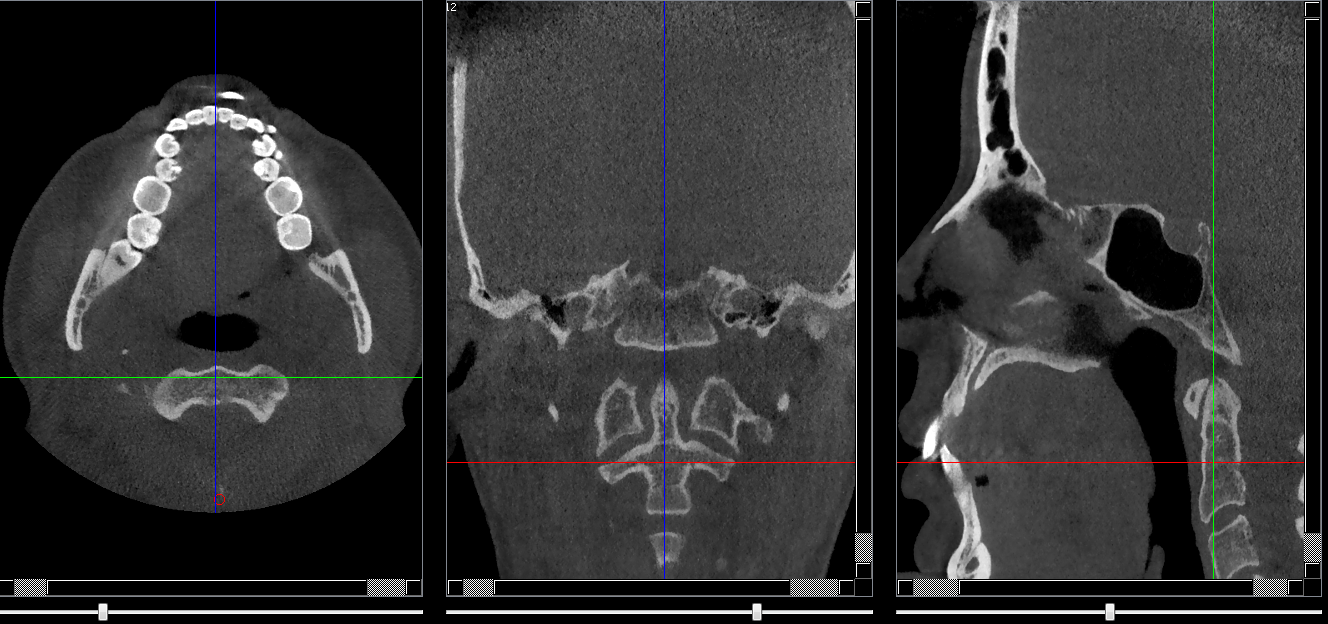

Structures osseuses

Arc antérieur de C1

Repères anatomiques

- Coupe transversale

- Début : Clivus

- Fin : ARC C2

- Coupe frontale

- Début : Partie post du sinus sphénoide

- Fin : Partie post du clivus

- Coupe saggitale

- Début : Processus clinoide droit

- Fin : Processus clinoide gauche

Infos sur l'image

- Auteur : Pr Bourzgui

- Co-auteur : Dr Makoure

- Affiliation : Orthopédie dento-faciale

- Date production : 2019